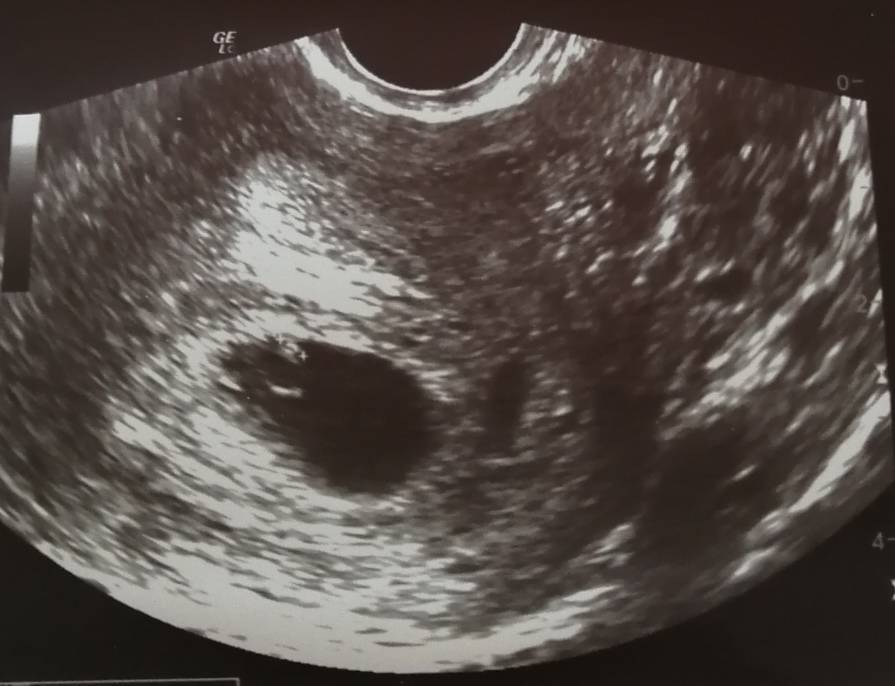

GratulacjeCiaza potwierdzona, jest pecherzyk, badania zlecone, termin ok. 4 kwietnia

Paola który tydzień u Ciebie?? Ja dziewczyny byłam na wizycie i z mies wychodzi 4 tydz. 4dni na usg sam pęcherzyk. Doktor mówi ze to normalne w tym tygodniu i za 3 tyg mam przyjść a ja już czarne myśliNo i jeszcze zdjęcie, mam nadzieję, że się dopatrzycie tego mojego malutkiego kropka [emoji3059]Zobacz załącznik 1013467

U mnie 5+5 z tego co dziś wyliczyła [emoji6] spokojnie jak pójdziesz po tych trzech tygodniach to już będzie i zarodek i serduszko zobaczysz [emoji6]Paola który tydzień u Ciebie?? Ja dziewczyny byłam na wizycie i z mies wychodzi 4 tydz. 4dni na usg sam pęcherzyk. Doktor mówi ze to normalne w tym tygodniu i za 3 tyg mam przyjść a ja już czarne myśli